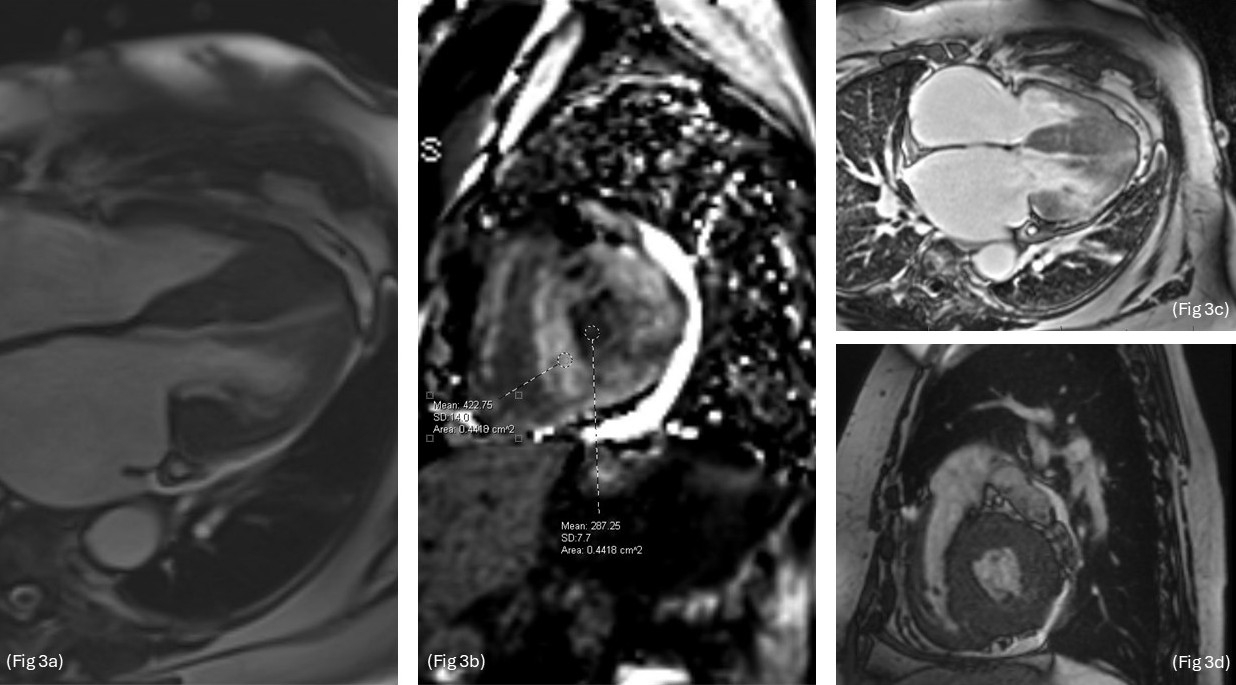

The patient was started on IV amiodarone, which resolved the SVT and NSVT, though she remained in Afib with RVR. Anticoagulation with IV heparin was initiated. Cardiology consultation recommended continuation of IV amiodarone, beta blockers, and anticoagulation. TTE revealed asymmetric left ventricular hypertrophy (LVH) involving the apex, suggestive of HCM, and severe biatrial enlargement (Fig 1 – 2). Of note, the patient had a family history of Fabry disease.

A TEE-guided cardioversion was performed, resulting in temporary restoration of sinus rhythm. Coronary angiography demonstrated mild non-obstructive CAD and normal filling pressures. She was discharged on oral amiodarone and metoprolol, with a plan for outpatient cardiac MRI.